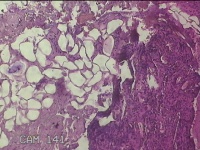

右侧耳垂结节

性别

男

年龄

24岁

临床诊断

耳垂新生物

一般病史

发现右侧耳垂结节3个月余。

标本名称

大体所见

灰白暗红色结节0.5x0.3x0.2cm一个,表面糜烂。

图1